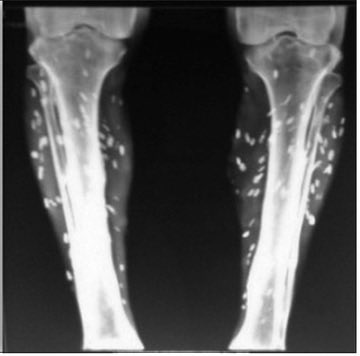

Twice a month mix 3 milliliters in a glass of Orange juice and down it. REMEMBER WHEN the Media laughed and said ivermectin was ONLY for horses and cows? THEY KNEW it was made for people since 1987.

Here’s what they didn’t tell you 👇

1 – It prevents the damage caused by drugs created using mRNA technology, blocks the entry of Spike Protein into cells and, if the person was vaccinated, they can treat themselves for damage already done through Ivermectin.

2 – It only has beneficial effects and no harmful effects in the treatment of the C virus. In fact, even before entering the cell, it has already destroyed the virus in the blood.

3 – It has a very powerful anti-inflammatory action against and has a powerful impact on traumatic and orthopedic injuries, it strengthens muscles and has no side effects like corticosteroids.

4 –It treats autoimmune ailments such as: rheumatoid arthritis, ankylosing spondylitis, fibromyalgia, psoriasis, Crohn's disease, allergic rhinitis.

5 – It improves the immunity levels in cancer patients and treats Herpes Simplex and Herpes Zoster, plus reduces the frequency of sinusitis and diverticulitis.

6 – It protects the heart in cardiac overload. In an embolism for example, it prevents cardiac hypoxia because it stimulates the production of basic energy so that the tissue is not destroyed and thus improves cardiac function.

7 – It is anti-parasitic, anti-neoplastic (anti-cancer). Allegedly, it suppresses the proliferation and metastasis of cancer cells, preserving healthy cells and improving the effectiveness of chemotherapy treatment.

8 - It can kills cancer cells resistant to chemotherapy, defeating the resistance to multiple chemo-therapeutics that tumors develop, and combined with chemotherapy and/or anti-cancer agents, it provides an increase in the effectiveness of these treatments.

9 – It is antimicrobial (bacteria and viruses) and increases immunity.

10 – It reaches the Central Nervous System and regenerates the nerves.

11 – It helps to regulates glucose, insulin metabolism, cholesterol levels and reduces liver fat in steatose.

12 - It can be used as a prophylactic agent and has been associated with a significant reduction in infection, hospitalization and mortality rates due to C-19.